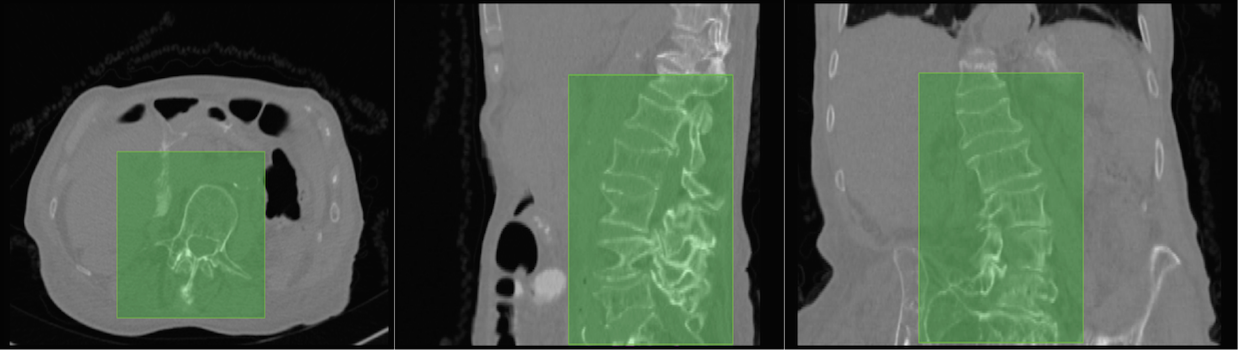

5.2 The Outlier (Case 25 of the xVertSeg Dataset)

As mentioned in section 3 (Lumbar localisation) of the main article, the localisation in Case 25 occurs with a sensitivity of 0.94 (figure 6(c), red outline) as it is the only example in the train and test data that consists of three sacral bones (S1, S2, and S3) within the field-of-view (figure 6(a)). When the scan, with S3 manually cropped off, is used as input (figure 6(b)), the lumbar localisation is perfect (sensitivity of 1.0), as shown by the green outline in figure 6(c). It is clear that the improper localisation is a consequence of working with limited data, and can easily be averted by increasing the variability in the training dataset.

Refer to caption

Figure 6: (a) Actual Case 25. (b) Case 25 with S3 cropped off. (c) Red and green regions correspond to lumbar localisation using (a) and (b) respectively. Blue is the overlap in the regions. Both the bounding boxes are overlaid on the original image.